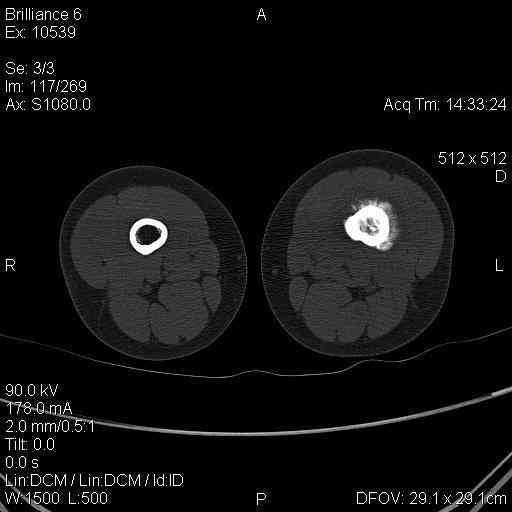

Мальчик 8 лет. Жалобы на боли в левом бедре. Со слов мальчика, ударился бедром несколько недель назад, после чего и начались боли.

В общем-то, диагноз сомнения не вызывает злокачественная опухоль, вероятнее всего - остеогенная саркома. У нас возникла дискуссия по поводу того, нужно ли брать открытую биопсию для гистологического подтверждения диагноза, либо сразу направить ребёнка в специализированный центр. С одной стороны, диагноз должен быть подтверждён гистологически. С другой - каждое нерадикальное вмешетельство на опухоли увеличивает вероятность метастазирования. В литературе чаще встречается такой подход - пациента сразу направляют в специализированный центр, где ему проводят как биопсию, так и дальнейшее лечение. Хотелось бы узнать мнение уважаемых коллег.

It could be Ewing sarcoma-its diaphyseal

Судя по представленным снимкам, нужно подумать о саркоме Юинга, так как Остеогенная саркома редко поражает диафиз трубчатых костей. Ее излюбленно место - метаэпифиз.